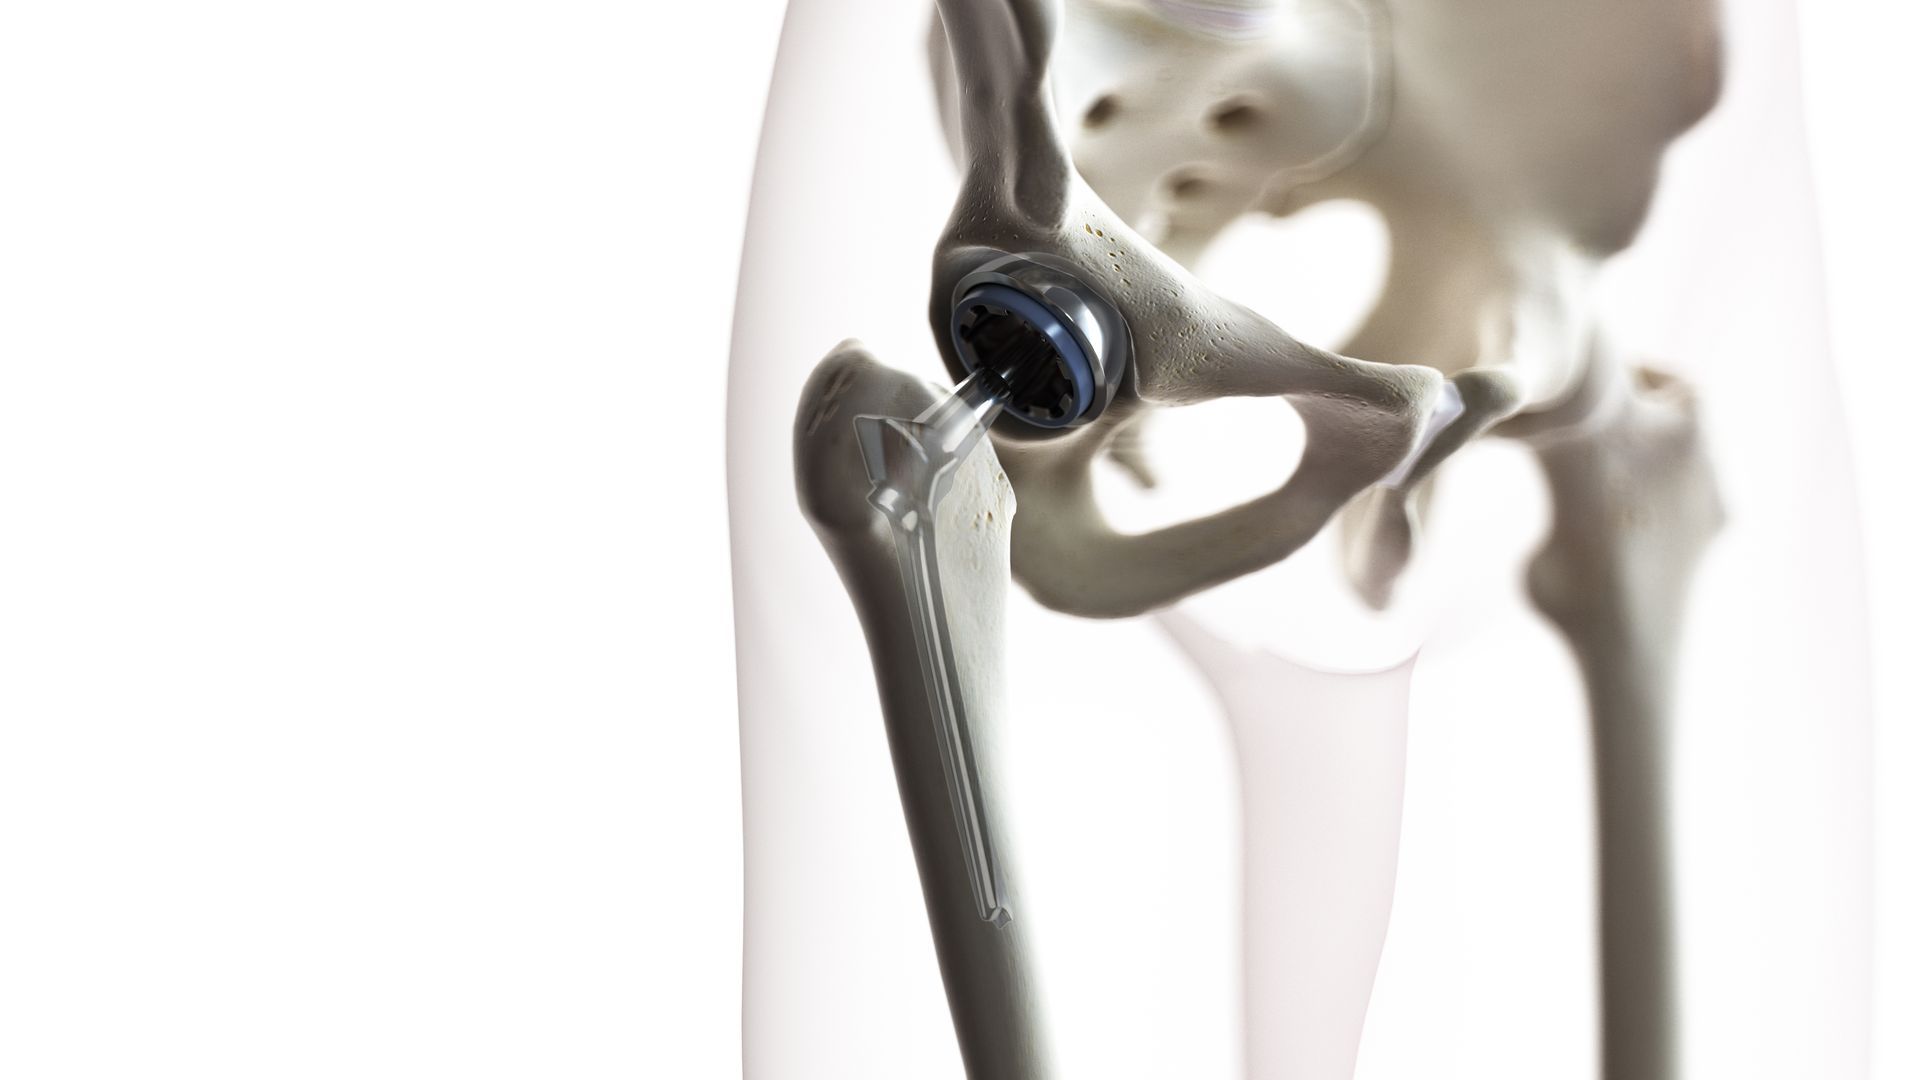

Com mais de 5000 cirurgias realizadas e mais de 1500 artroplastias de sucesso, meu compromisso é ajudar pacientes a recuperarem sua qualidade de vida, combinando competência técnica com valores de seriedade e honestidade.